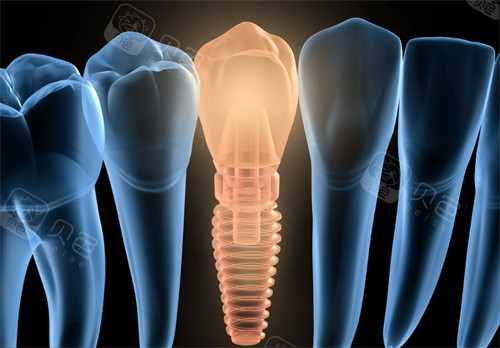

显微镜根管治疗系统全蒙自没几家有,钙化根管、根尖囊肿都能精细处理。CBCT机拍出来的三维影像,连神经管位置都清晰可见。

青少年矫正用3Shape扫描仪,2分钟生成牙齿模型,家长能手机查看矫正进度。种植牙手术用三星全景CBCT,精度0.1mm,避开血管神经。

引进隐适美迭代版口扫仪,取模精度提升30%。种植牙用动态导航系统,植体角度误差控制在0.5度内。